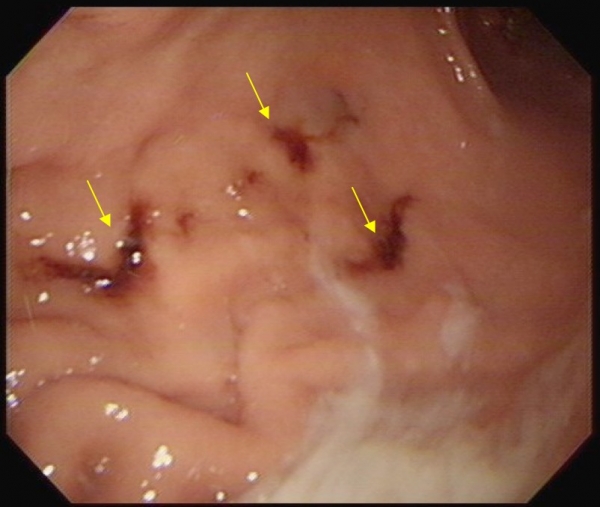

5.幫助控制胃潰瘍:

當你有胃潰瘍的時候,其實有很多食物都是不能吃的,但可以吃香蕉喔!因為香蕉可以提供胃一層薄薄的保護膜,幫忙擋住胃酸跟胃受刺激。